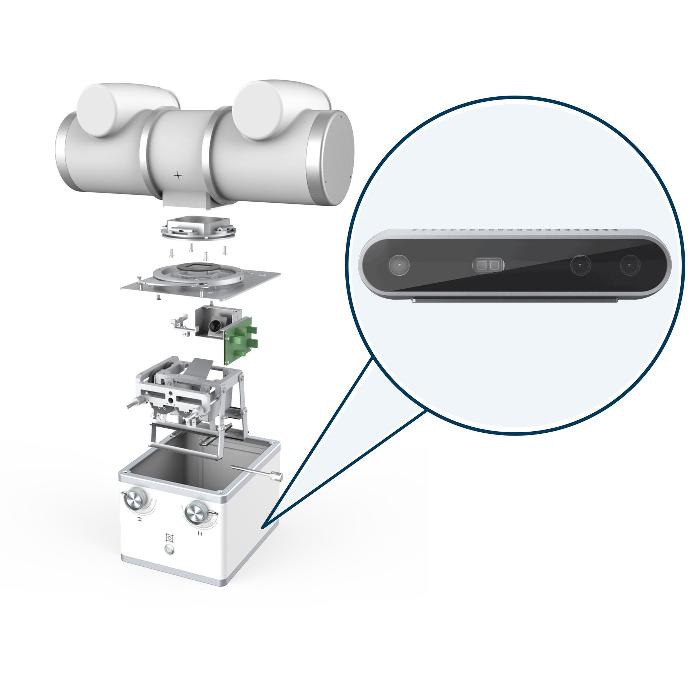

Système radiographique vétérinaire VETSMART DR